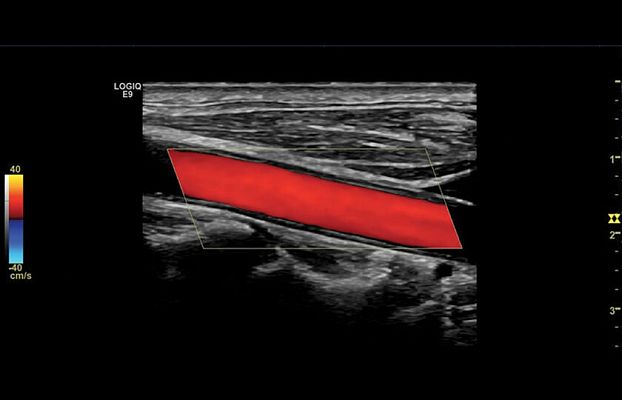

Клинические изображения

- B-Flow и Color B-Flow — технология прямой недопплеровской визуализации кровотока в режиме реального времени, которая позволяет получить гемодинамический профиль с повышенной чувствительностью и разрешением без нежелательных сигналов от окружающих тканей в сосудах всех типов, от крупных, например, сонной артерии, до мелких, например, сосудах паренхиматозных органов.

- Auto IMT — автоматическое измерение толщины комплекса «интима-медиа».